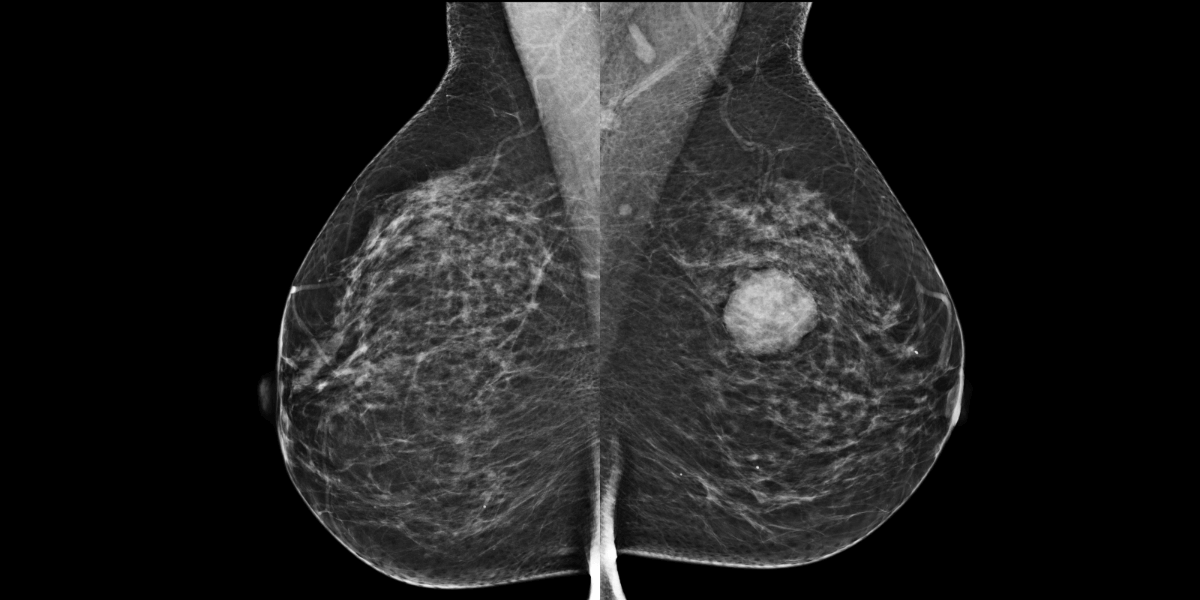

Femme de 60 ans, examinée pour tuméfaction supéro-externe du sein gauche.

MammoScreen™ pointe une masse suspecte (Score de 5) du sein gauche.